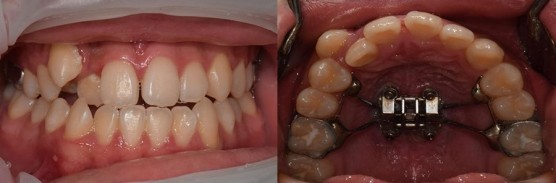

[상악구개확장장치 장착 시 구강 내부 모습 (2022.01.25)]

일반적인 교정보다는 힘들겠지만 입천장에 위와 같은 형태로 장치를 고정하고 나사를 돌리며 악궁을 벌려주는 원리입니다.

자 이제 돌리기 시작합니다.

[상악구개확장장치를 이용한 부정교합 치료 전/후 비교]